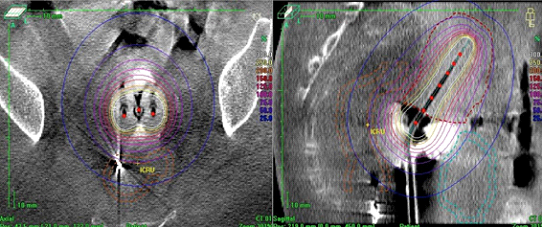

当院はイリジウム(I92lr)小線源を用いたRALSを導入し、主に、子宮頸癌に対する小線源治療を行っています。最近では、コーンビームCTの三次元画像データを応用した小線源治療の最適化(画像誘導小線源治療)に取り組んでいます(上図:治療寝台上での三次元画像データ取得、下図:線量分布図)。

子宮内に補助器具を挿入し(左図:X線撮影像)、計算された停留位置と停留時間に基づいて遠隔操作で線源を移動させ病巣部を照射する(右図:線量分布)。